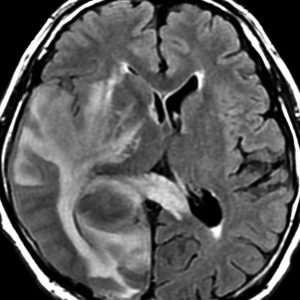

これは1990年代の古い例ですがリンパ腫の増大が早いことをお見せします。左側のはTHP-COPという化学療法をする前のものです。真ん中のは化学療法から4日目で,腫瘍は小さくなりました。でも,2コース目の化学療法の直前(4週間後)にもう一度MRIをしてみたらすごく大きくなっていました。この化学療法は効いているのだか効いていないのだか判らないことになります。化学療法を行なうならとても強い薬剤を使わなければなりませんし急がなければなりません。